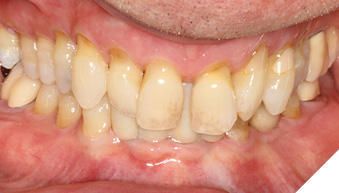

A 65-year-old woman comes to the office with the chief complaint of worn-down teeth, missing teeth, tooth sensitivity, especially on maxillary teeth and TMJ pain. Her past medical history was reviewed and was significant for asthma, insomnia, hypercholesterolemia, hypothyroidism, and anxiety disorder. She denied any sleep disturbances. Her medications included salbutamol, ezetimibe, quetiapine, and levothyroxine. She referred to being allergic to dust and shellfish and sensitive to propofol. She had a right mastectomy in 2014 due to breast cancer. No chemotherapy or radiation was done. Her diet was considered normal, and she denied any consumption of acidic drinks and denied any history of regurgitation. She denied any parafunctional habits during the day. She was using a maxillary transitional partial denture since she had lost some of her teeth due to fracture and caries. No other problems were evidenced. Intraoral exam showed moderate attrition lesions of posterior teeth, porcelain fused to metal crowns on teeth 46 and 47 had the porcelain portion worn down, exposing the metal substructure. Missing teeth included teeth 14,15,16,18,24,28, 36,38,48. Palatal surfaces of maxillary anterior teeth also appeared worn down. An abfraction lesion was found on tooth 23. No carious lesions were found in any of her teeth. Composite restorations on mandibular anterior teeth were chipped or were missing (Figs. 6-11) She also presented with limited mouth opening: 35 mm interincisal distance at maximum opening. There was bilateral pain on palpation of preauricular areas. Her pain was the worst early in the morning which suggested night parafunction. No crepitus, or joint clicking were found.

Articulated diagnostic casts showed very limited to no overjet and 90% of overbite. The wear pattern on the palatal aspect of her maxillary teeth appeared to be secondary to her tight occlusion since mandibular anterior teeth were in close contact with these surfaces with no “room” for protrusive movements. The diagnosis for this patient was: partial edentulism, failing existing restorations and attrition and abfraction secondary to parafunction. We discussed different options, including orthodontics in order to increase her overjet so we could have prosthetic space to restore her worn down teeth. We also discussed tooth replacement options. After a second consultation appointment which she attended with her husband, she decided that she did not want to replace her teeth with removable prosthetics. She also declined referral to an orthodontist. After discussion of multiple options of treatment to address all her chief complaints, her treatment consisted of a full mouth reconstruction with full coverage restorations in Zirconia for teeth 11-13,17,22-23,25-27,32-42, 44-47 and partial coverage restorations with lithium disilicate restoration for teeth 33,34 and 43. Replacement of teeth was achieved with a fixed partial denture to replace tooth 36 and a 3-unit implant supported bridge to replace teeth 24-26. In terms of occlusion, we created a more favorable occlusion with a proper anterior guidance, canine disclusion with more freedom for protrusive movements, which hopefully would decrease the parafunction, and alleviate some of her muscle pain. Before completing the case, the patient spent several weeks with provisional restorations which reflected the increase in vertical dimension of occlusion and the new occlusal scheme. During this trial phase, we assessed comfort, esthetics, function, decrease in pain and speech (Figs. 12-17).